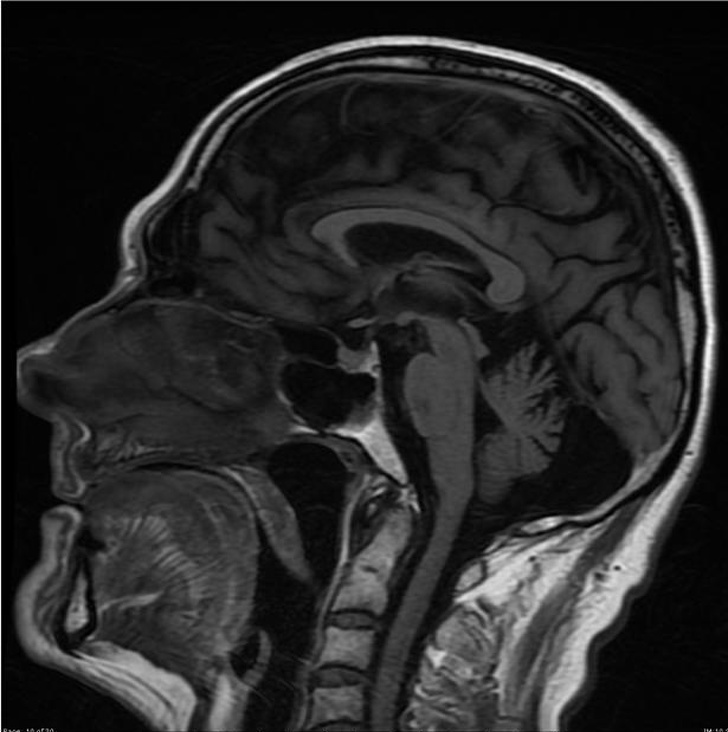

14. Пацієнт з алкогольним ураженням мозку. З-за впливу спиртних напоїв головний мозок і мозочок зменшилися в розмірах